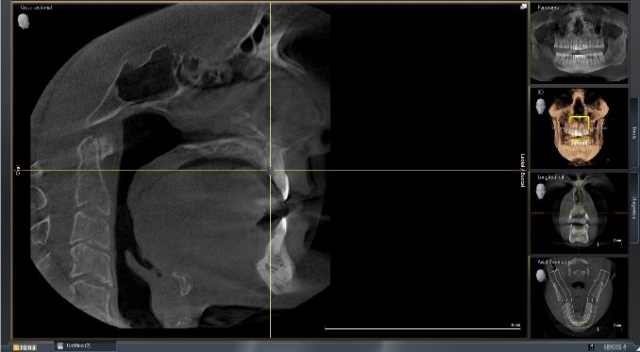

If you are planning on using software like SicatAir to compare airway volume at that position compared to maximum intercuspation, then it might be a good idea to leave the silicone, and you could even take out the lower part of the bite fork, allowing the patient to bite solidly into the material (Figs. 9–12).

That entire digital file can then be uploaded and sent to fabricate an appliance, capturing the position of the mandible, while confirming the anticipated volume (yes, I know the patient is awake and sitting up. If you find a way to take a scan with the patient supine and asleep, it would be even better, right?) (Fig. 13)